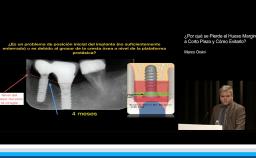

Complicaciones Mecánicas en Prótesis Implantosoportadas con Cantilevers

En esta conferencia, la Dra. Iria López habla acerca de las complicaciones que pueden presentarse en prótesis diseñadas con cantiléver. La Dra López lleva su exposición de una forma organizada, en la que primero, fundamenta la relevancia del tema y la frecuencia con la que este tipo de tratamientos se llevan a cabo. Posteriormente hace un análisis tanto de las diferentes circunstancias en las que un cantiléver puede ser utilizado y el tipo de complicaciones protésicas que se pueden presentar. Muestra una excelente selección de artículos que brindan evidencia no solo de las complicaciones protésicas, sino incluso del comportamiento biológico de los implantes que soportan este tipo de prótesis.